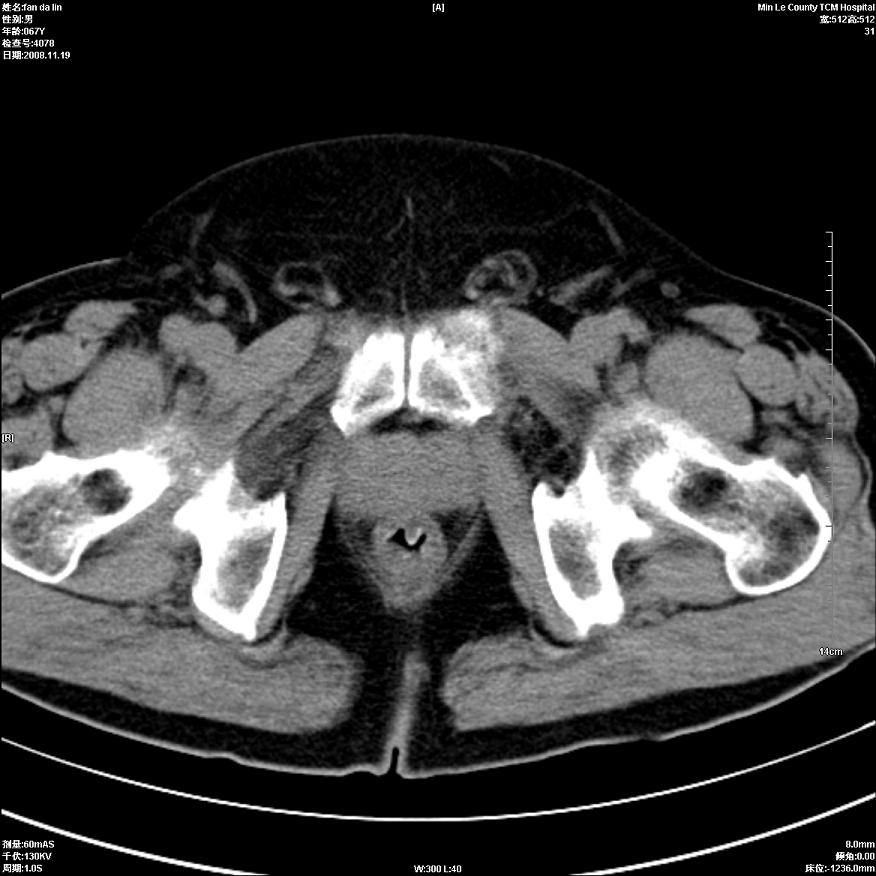

标题: CT16698:M67Y,看看直肠下端是不是病变 [打印本页]

标题: CT16698:M67Y,看看直肠下端是不是病变

未见明确异常.建议:必要时行指诊.

建议肛诊。

充盈可,尚增厚高度怀疑,建议肛诊!

只是肠壁局限性增厚,但难说明问题。